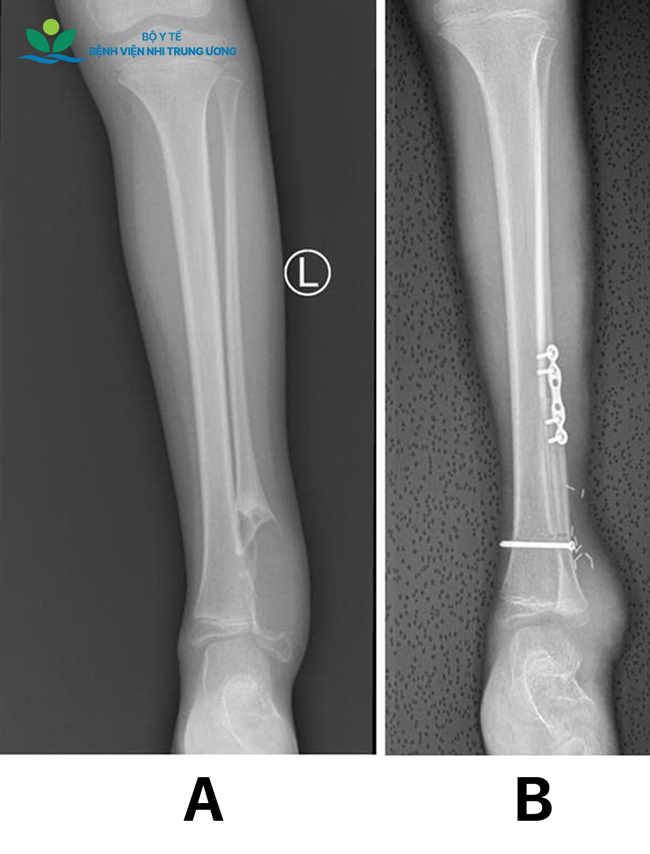

Kết quả thăm khám và chẩn đoán hình ảnh cho thấy khối u Chondrosarcoma (u sụn ác tính) tái phát ở đầu dưới xương mác bên trái (toàn bộ mắt cá ngoài bị tổn thương), kích thước lớn, chèn ép sát các cấu trúc mạch máu và thần kinh quan trọng vùng cổ chân. May mắn, các kiểm tra chuyên sâu xác định bệnh chưa di căn các cơ quan khác. Các bác sĩ đã tiến hành cắt bỏ toàn bộ khối u đầu dưới xương mác trái theo nguyên tắc ung thư xương, giải phẫu bệnh cho kết quả diện cắt âm tính (R0) — điều kiện then chốt để giảm nguy cơ tái phát tại chỗ.

Hình ảnh X quang:(A) trước mổ cắt u; (B) sau mổ ghép vạt xương